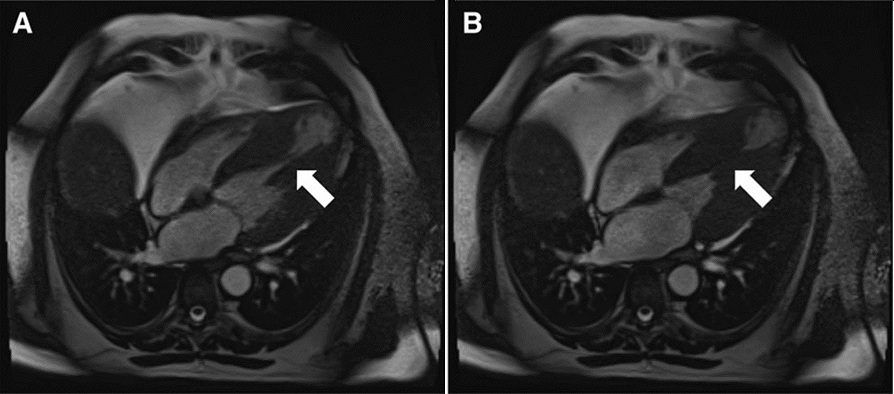

为了解答这些疑问,安排了心脏MRI检查。心脏MRI显示(图3),室间隔明显增厚,收缩期左室腔消失,同时我们注意到,心尖部室腔在收缩期未向内收缩,而是向外扩张,证实了的心尖部室壁瘤的存在。

图3 心脏MRI

,合并心尖部室壁瘤,室壁瘤可能来自于心肌肥厚后出现的纤维瘢痕,而室壁瘤则构成了室速的基质,围绕着室壁瘤的折返是室速发作的原因。再回头去看图1A的心电图,发现除了aVR和aVL外其余导联的QRS波均为负向,说明激动起源自心尖部,传向心底,和室壁瘤的位置是吻合的。这也解释了为什么患者V4-V6导联没有病理性Q波,以及反复冠脉造影的阴性结果。